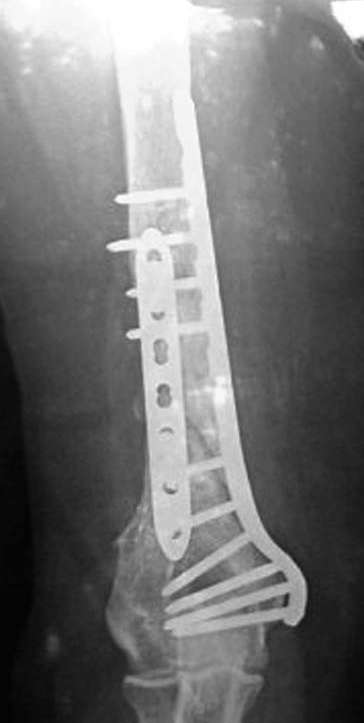

Второй случай, также после множественных операций:

пластина, аппарат, серкляж и парез нерва.

Также ревизия, из-за низкого состояния доступ был

сделан через остеотомию локтевого отростка.

Ложный сустав фиксирован двумя локинг плейт с

аутокостной пластикой, также через два месяца увидели признаки консолидации.

Движение в суставе разрешили в две недели.